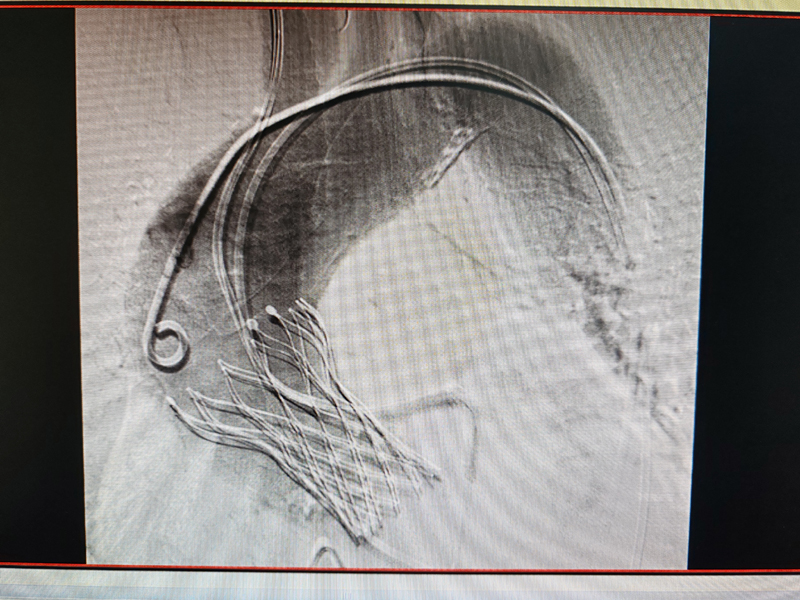

主动脉狭窄 TAVR手术

心血管内科作为衡阳市医学会内科专业委员会主委单位及心血管内科专业委员会主委单位,2019年获批衡阳市心力衰竭防治重点实验室建设项目,2021年获批湖南省动脉硬化性疾病临床医学研究中心,2022年获批湖南省省级临床重点专科,目前结合心血管六大中心,四个病区,在IVUS引导下的冠脉精准个治疗、ECMO+IABP辅助循环支持下危重症患者的冠脉介入治疗、心脏瓣膜病TAVAR治疗、恶性心律失常的三维标测治疗、心血管疾病的危重症患者康复治疗等方面做到省内领先!